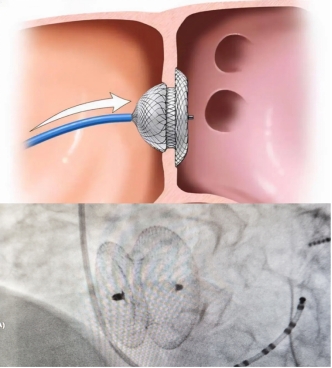

王召军教授将“接力棒”交到涂应锋教授手上,两项手术共同利用股静脉通路,避免患者二次损伤。在心脏超声医师郭耀磊的“最强辅助”下,涂应锋教授根据患者心脏彩超结果,选用合适大小的30mm房间隔封堵伞,成功堵住患者的“小心眼”,术后心脏彩超评估封堵十分成功。